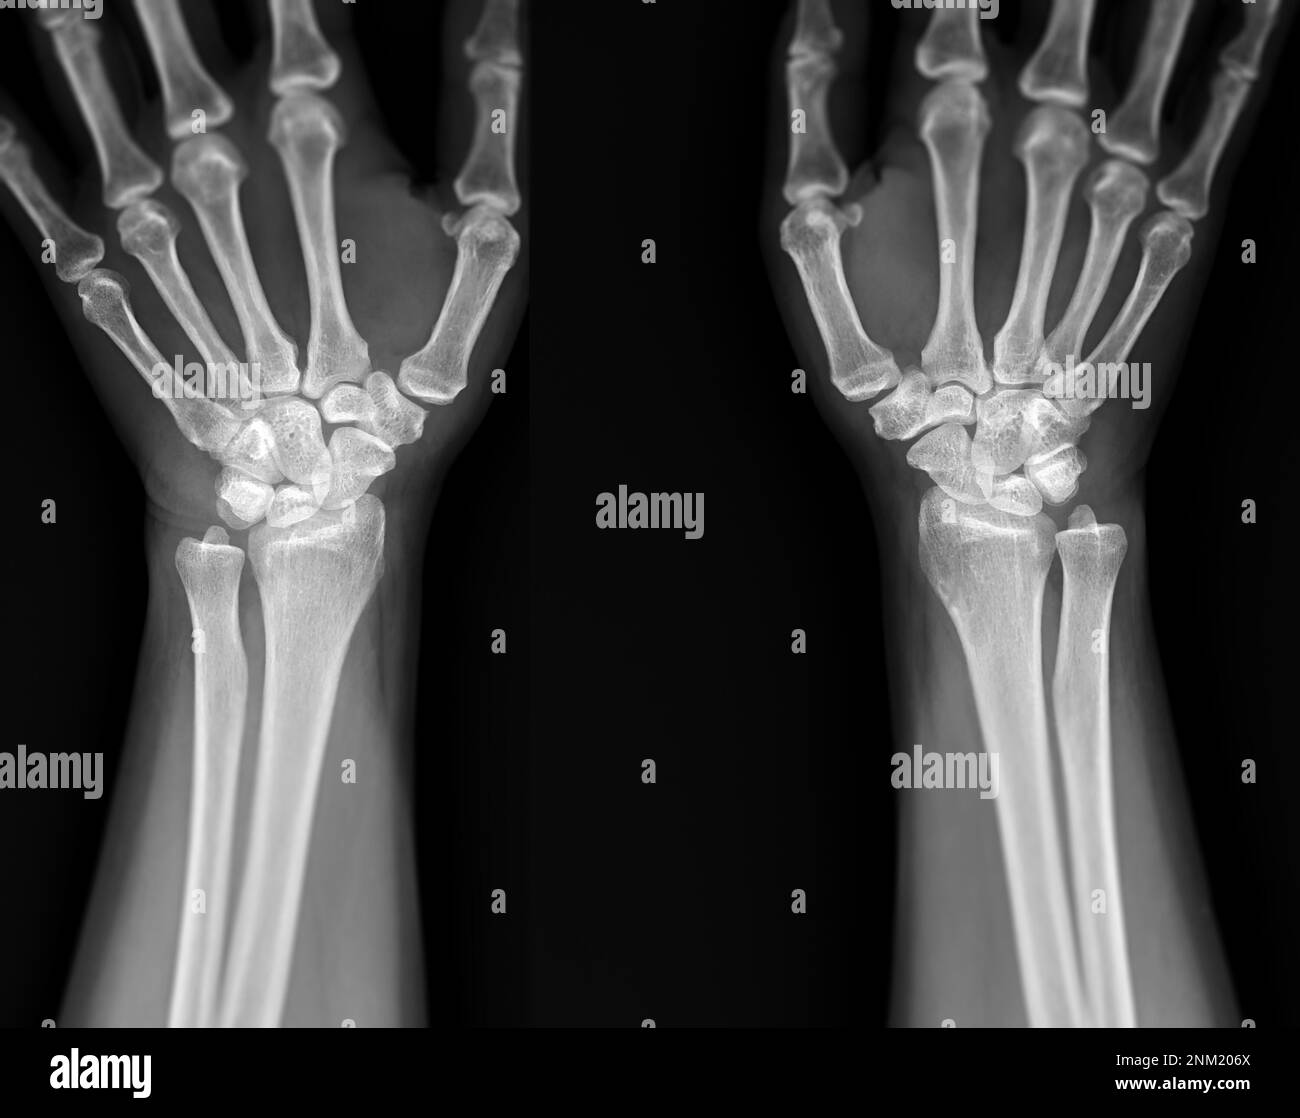

From stock.adobe.com

Hand wrist xray Stock Photo Adobe Stock How To Read Hand Wrist X Ray A systematic approach to reviewing hand radiographs, including soft tissue, cortical margins, trabecular patterns, bony alignment,. Order of ossification (clockwise in a right hand starting at capitate): Additional or repeat views may be required for suspected injury of other carpal bones. About press copyright contact us creators advertise developers terms privacy policy & safety. Capitate, hamate, triquetrum, lunate, scaphoid, trapezium,. How To Read Hand Wrist X Ray.